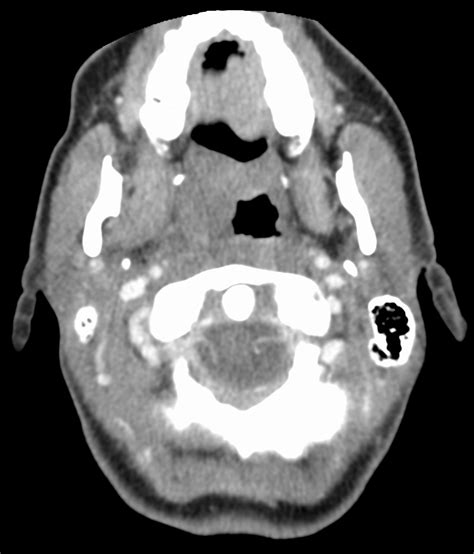

So, what exactly is CT FFRe analysis ? In simple terms, it’s a non-invasive way to figure out how blood flow is affected by blockages in your coronary arteries. Traditionally, doctors had to use invasive methods like cardiac catheterization to get this information. That means inserting a catheter into an artery and threading it up to the heart. While effective, it comes with risks like bleeding, infection, and is generally more uncomfortable for the patient. CT FFRe analysis, on the other hand, uses advanced CT scan technology combined with sophisticated software to simulate the pressure and flow changes that would occur if a wire were placed in the artery. It’s like having a virtual test run without any of the physical invasiveness. This analysis gives doctors crucial data about the functional significance of any narrowing detected on a standard CT coronary angiogram (CTCA). It helps them determine if a blockage is actually causing a significant reduction in blood flow, which is key to deciding whether a patient needs treatment like stenting or bypass surgery, or if they can be managed with medication. The evolution of CT FFRe represents a major leap forward in cardiology, offering a safer, more convenient, and often more cost-effective alternative to invasive procedures for assessing coronary artery disease. It’s all about providing the best possible care with the least amount of patient burden.

Alright guys, let’s get into the specifics of the CPT codes for CT FFRe . It’s important to understand that CT FFRe is often performed in conjunction with a standard CT coronary angiogram (CTCA). Therefore, you usually need to report both the imaging procedure and the interpretation/analysis of the flow reserve. The primary CPT code for the interpretation and reporting of CT FFRe analysis is 75574 . This code specifically covers the ‘Image-based noninvasive fractional flow reserve (FFR) derived from coronary computed tomography angiography (CTA); interpretation and report’ . So, when you’re billing for the analysis part of the CT FFRe, this is your go-to code. However, remember that the CTCA itself needs to be reported. The CPT code for the coronary CT angiography is typically 71275 ( ‘Computed tomography, thorax; angiography, coronary artery, with contrast, non-coronary cardiovascular angiography’ ) or sometimes 70470 ( ‘Computed tomography, orbit and skull; without contrast material’ ). It’s crucial to check the payer’s specific guidelines, as they might have preferences or require specific modifiers. The combination of these codes paints a complete picture for the payer: you performed the imaging (CTCA), and you performed the advanced analysis of blood flow (FFRe). It’s vital to use 75574 only when the FFRe analysis has actually been performed and interpreted. Simply doing a standard CTCA does not warrant the use of this code. The distinction is key to maintaining compliance and avoiding any billing discrepancies. Always refer to the most current CPT codebook and any payer-specific updates to ensure you are using the codes correctly.